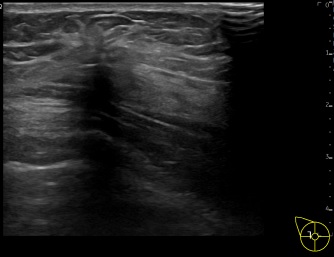

상기환자는 외부건진이상 유방외과 진료권유받아 내원하신 40대중반

여성분으로 의심스러운 우측혹 조직검사 시행해 유방암 진단되었습니다